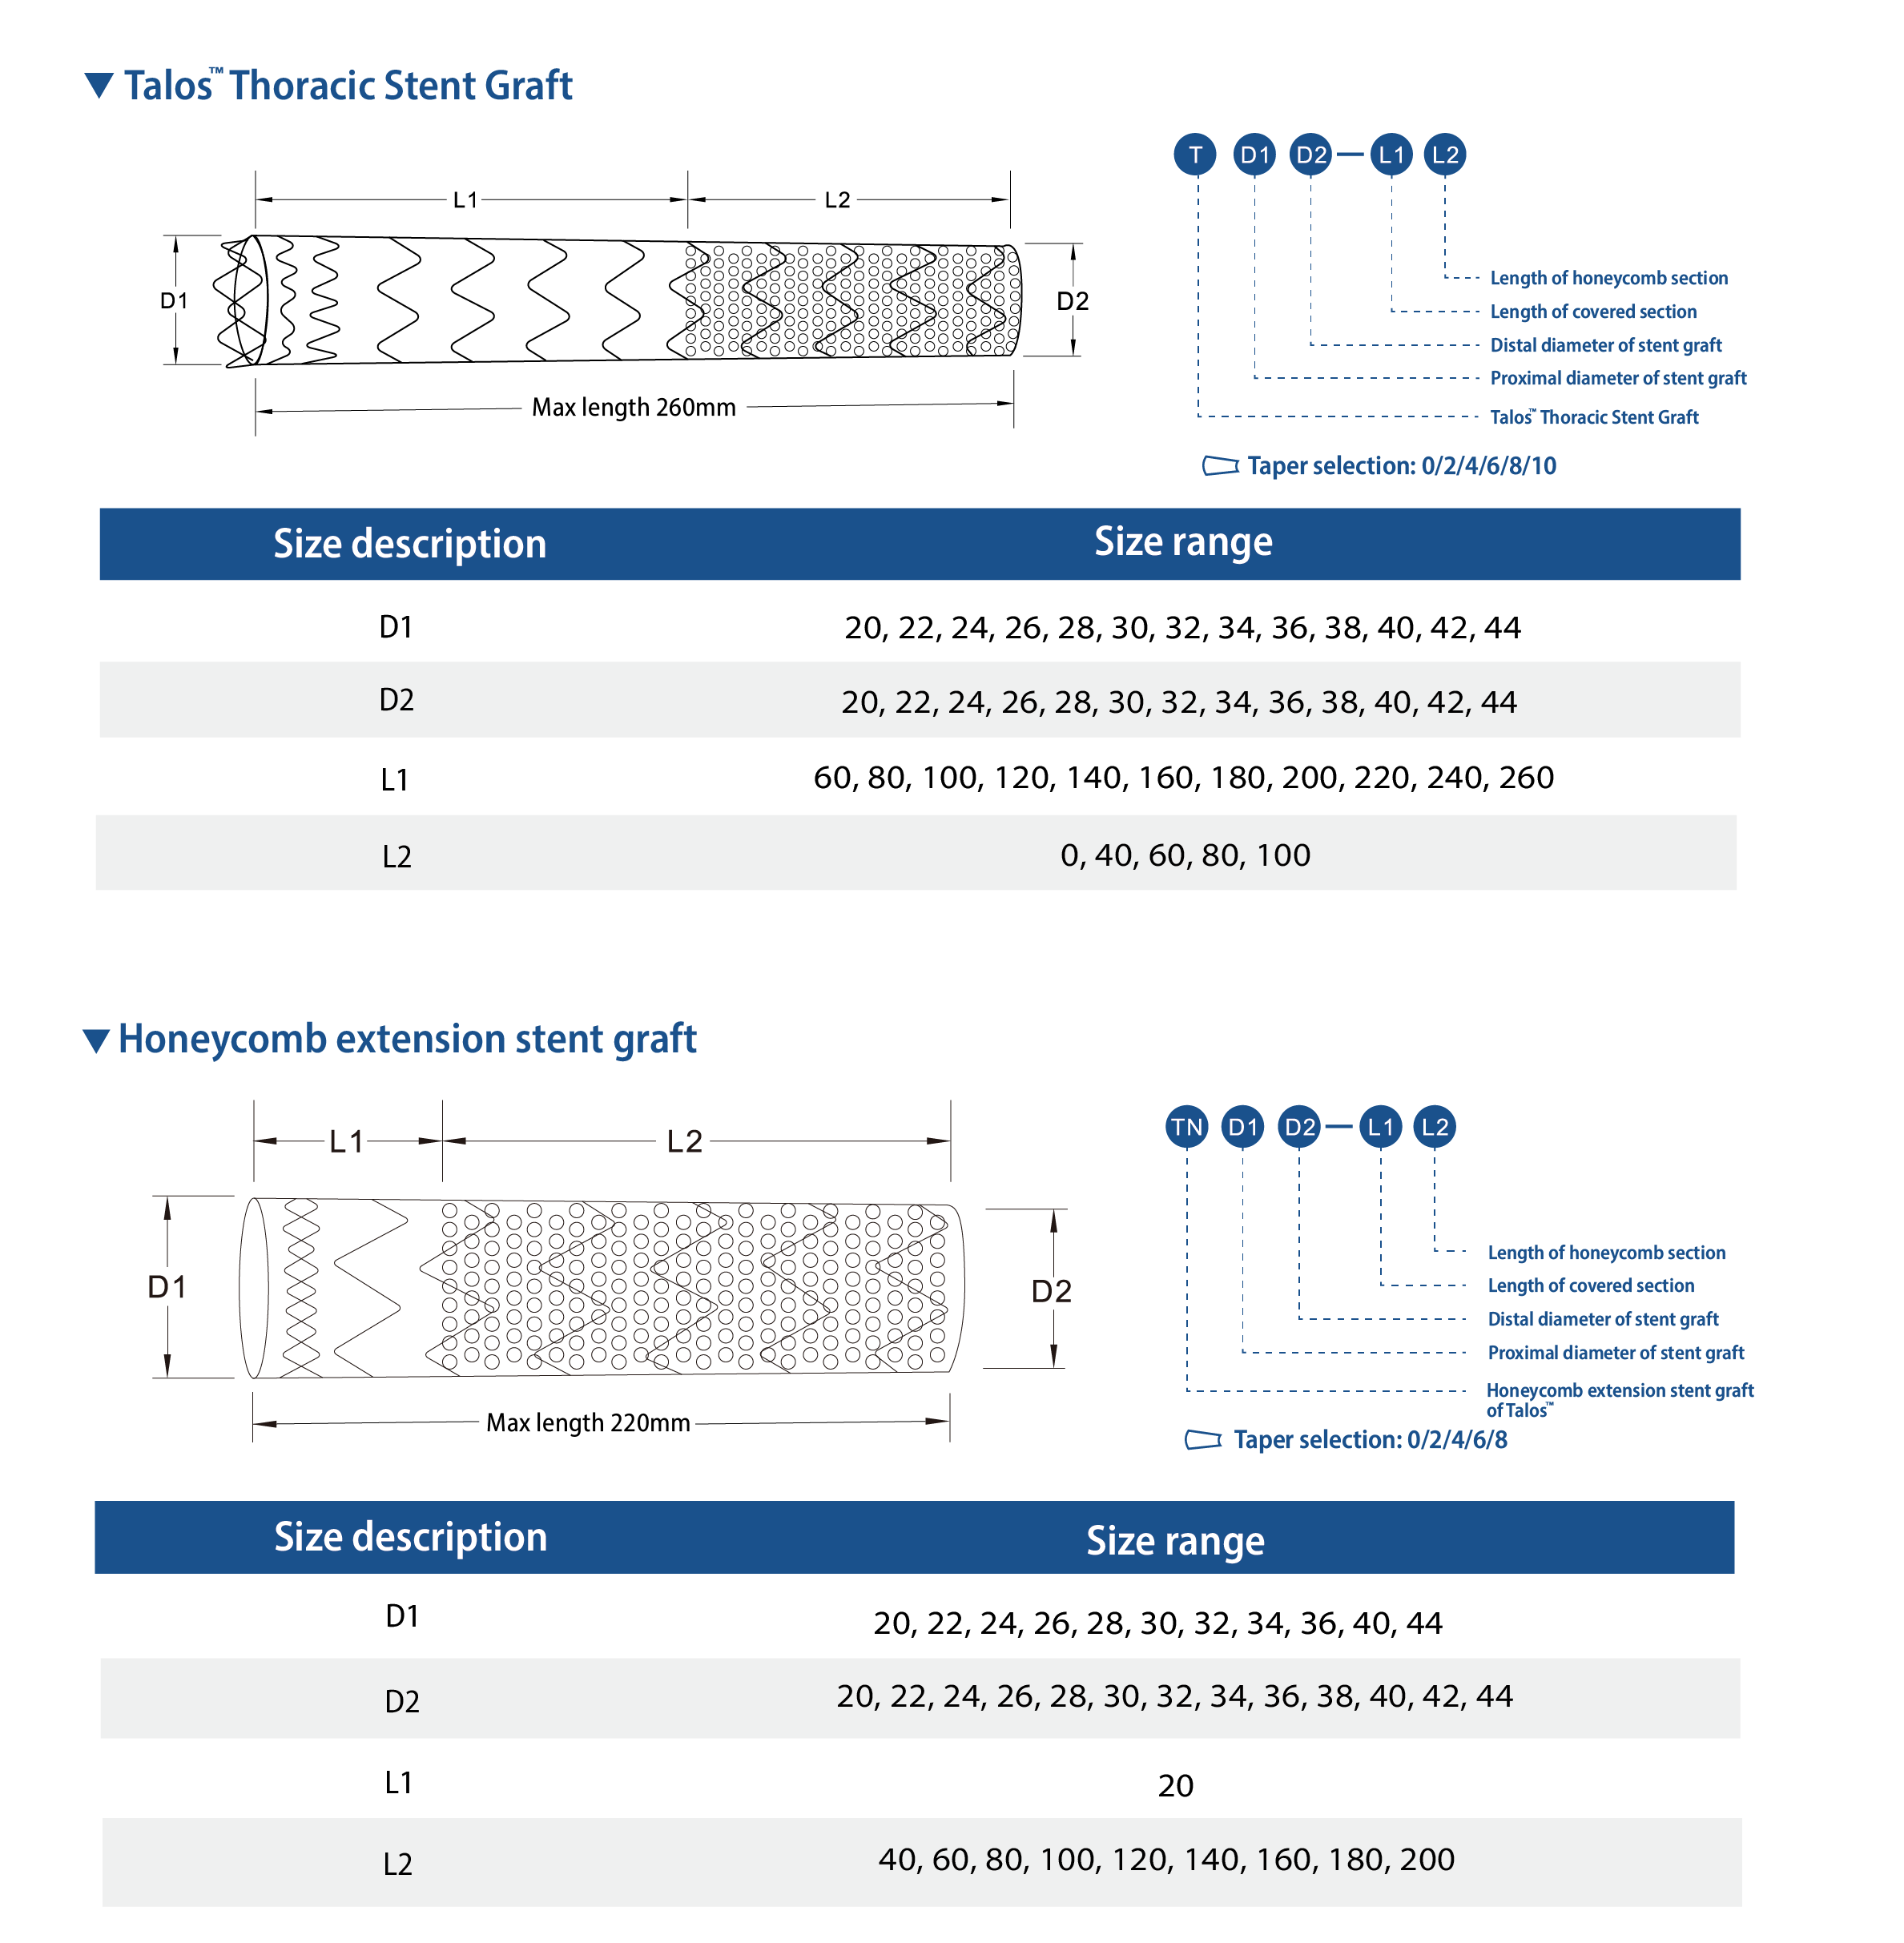

Specification Parameter